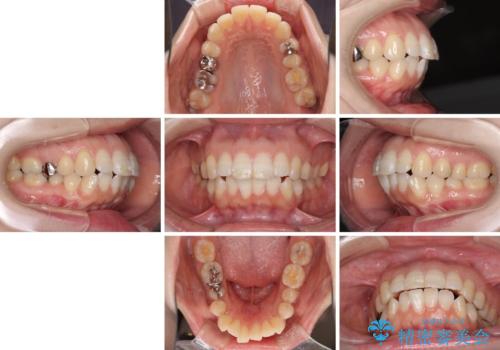

口元の突出感改善 なるべく銀歯を抜歯してワイヤー矯正

- 口元の閉じにくさと、前歯のでこぼこの歯並びを気にして来院された患者様です。

口元を積極的に引っ込めるために、上下左右の小臼歯計4本を抜歯することとしました。

セオリーでは第一小臼歯を抜歯しますが、上下右側は第二小臼歯に銀歯が装着されているため、第二小臼歯を抜歯することとしました。

上下正中を左右対称に揃えるため、アンカースクリューや補助装置を使用しながら口元を下げていくこととしました。

積極的に前歯を牽引したことで、口元の閉じにくさは顕著に改善され、横顔のシルエットが大幅に変化しました。